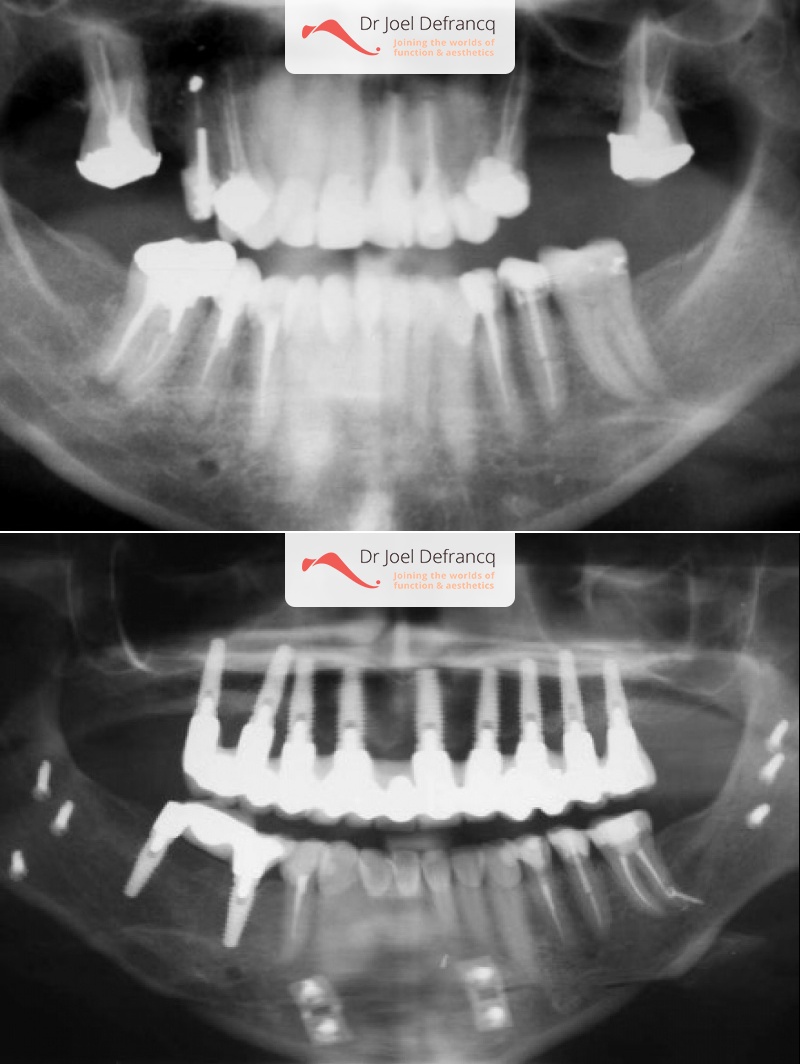

Kaakchirurgie

- Verlenging onderkaak (BSSO)

- Kinchirurgie

Behandeling tandheelkundige implantaten

- Vaste tanden op implantaten (bovenkaak)

- Implantaten met osteotomie

- Implantaten met beenopbouw